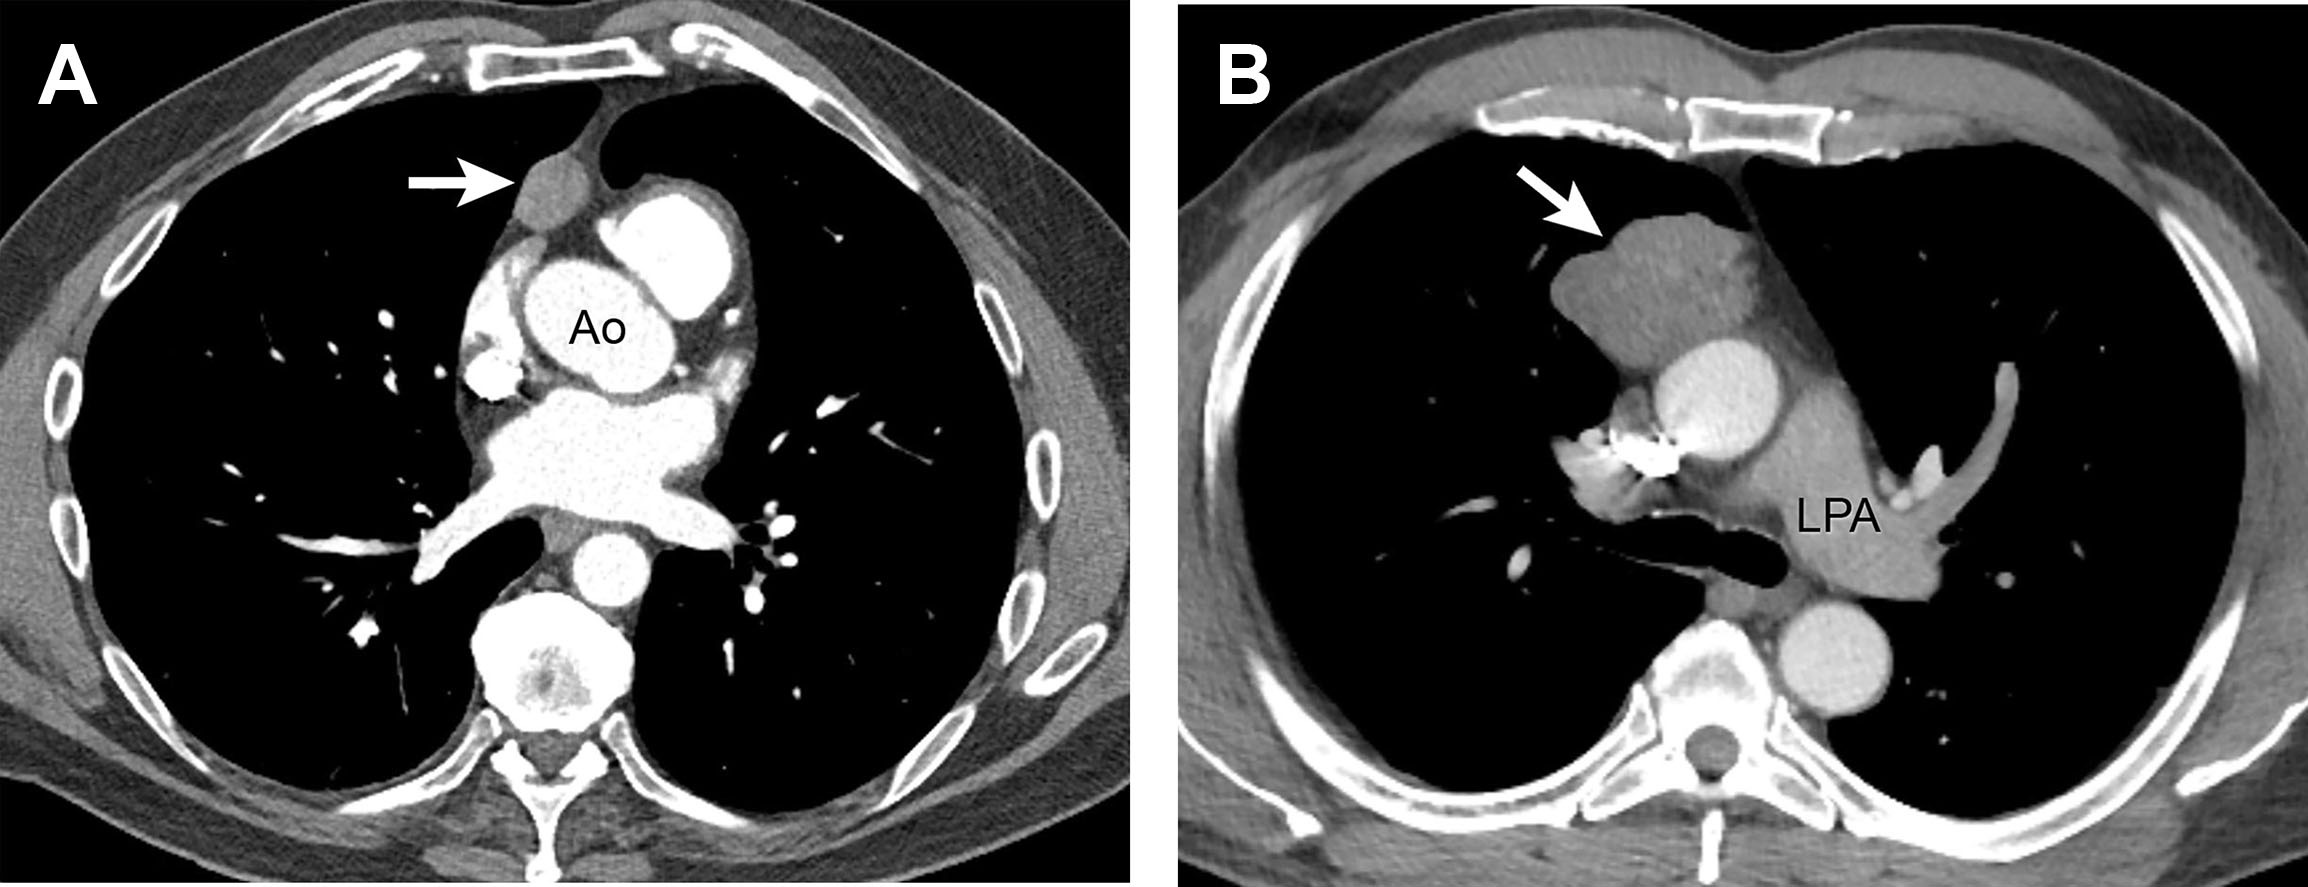

(PDF) Differential diagnosis of thymic epithelial neoplasms on computed Thymic Neoplasm Icd 10 Primary or metastatic malignant neoplasm involving the thymus. Primary or metastatic malignant neoplasm involving the thymus. C37 is a billable diagnosis code used to specify a medical diagnosis of malignant neoplasm of thymus. The clinical presentation, diagnosis, staging, and management. The code is valid during the current fiscal year for. Thymic tumors are rare neoplasms that arise in the anterior. Thymic Neoplasm Icd 10.

Differential diagnosis of thymic epithelial neoplasms on com... Medicine Thymic Neoplasm Icd 10 The code is valid during the current fiscal year for. This code description may also have includes , excludes ,. Thymoma is a tumor originating from the epithelial cells of the thymus. Primary or metastatic malignant neoplasm involving the thymus. This category includes malignant thymomas, thymic lymphomas, primary. The clinical presentation, diagnosis, staging, and management. Thymic tumors are rare neoplasms. Thymic Neoplasm Icd 10.